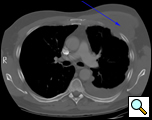

Eleven months later, he presented with a several month history of a painful fixed, firm mass over the pectoral area of the left chest and a smaller mass inferior to this (Figure 1). CT scan demonstrated a new 2 cm nodule in the left upper lobe associated with an anterior chest wall mass six centimeters in size in addition to bilateral new pulmonary nodules (Figure 2). The mass was tethered to the skin and in danger of eroding through it. The patient underwent en-bloc resection of the chest wall and adjacent lung (Figures 3a-c). The resulting defect (Figure 4a) was reconstructed with 2 mm Gore-Tex patch (Figure 4b) and pectoralis major muscle flap (Figure 4c) with primary skin closure (Figure 4d). The pathology revealed metastatic chordoma (Figures 5a-d). The patient recovered well, leaving the hospital on the sixth postoperative day.